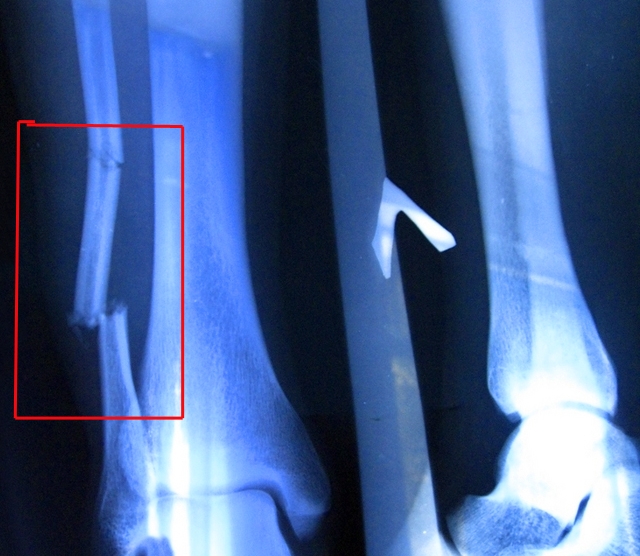

Рентгенография — один из самых доступных методов для исследования внутренних заболеваний. Этот метод используется не только при травмах, таких как переломы или смещения, но и при различных заболеваниях, включая артрит, артроз, плоскостопие и аномалии развития. В некоторых случаях, например, при деформации стопы или наличии метастазов, рентген становится основным инструментом для диагностики.

- наличие или отсутствие переломов;

- Рентгеновский аппарат пропускает рентгеновские лучи через мягкие ткани, подчеркивая кости ног и выявляя патологии костной системы. На снимках переломов видны не только нарушения целостности, но и расстояния между осколками, а также их количество в случае фрагментарного перелома. Увеличение изображения помогает диагностировать даже незначительные отклонения от бедра до мизинца.